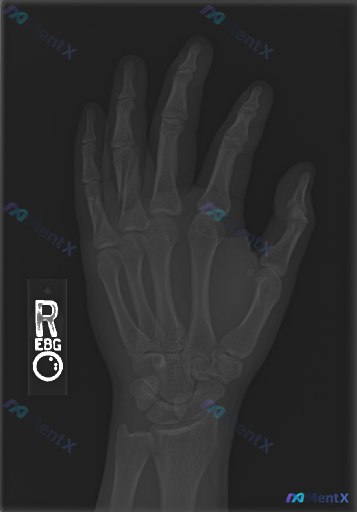

拿到一张右手正位X光片,你会怎么解读?

整理到一张右手正位X光片的读片资料: 影像客观表现: - 各指骨、掌骨、腕骨骨皮质连续,未见明确骨折线、成角畸形或骨质破坏区 - 各关节对位关系正常,关节间隙无明显狭窄或增宽,关节面光滑,无明确骨赘或侵蚀 - 骨周围软组织轮廓清晰,密度均匀,未见明显肿胀、钙化或异物影 - 整体骨密度大致正常,骨骺线...